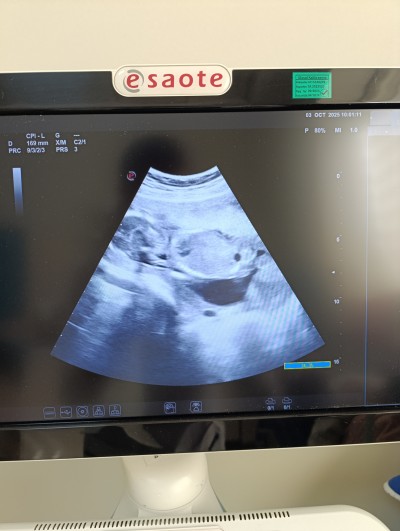

Merhaba kizlar ilk zamanlar özelde doktor ufak bı kanama gözüküyor dedi devlet gittim şuan 4 aylık pihtilasmis igne vuralım dedi yaşayan varmı düşünceleriniz nedir

Gebelik haftası 19